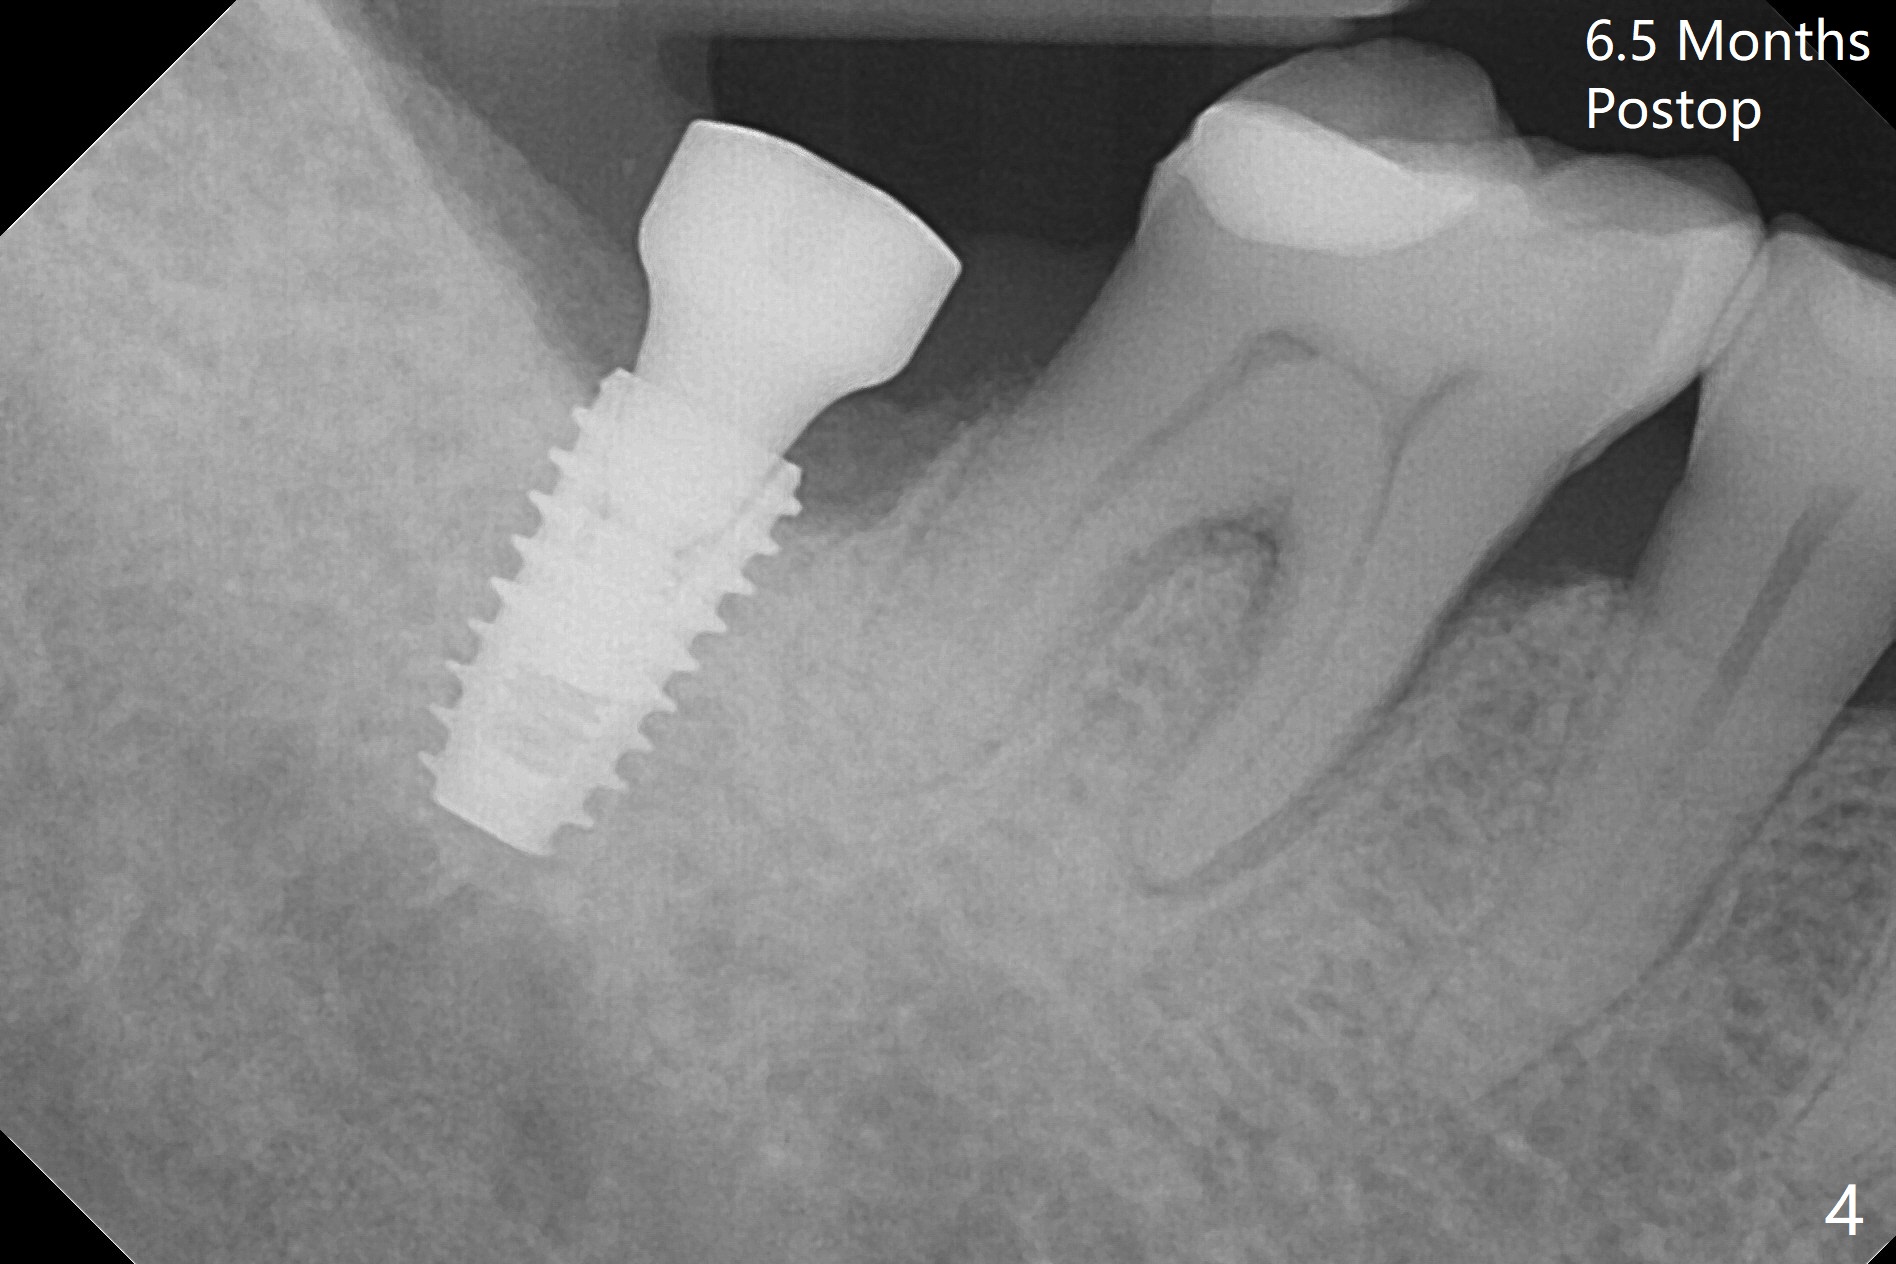

The ridge at #31 is wide buccolingually, but uneven with buccal lower. When a 3 mm drill reaches 13 mm in depth (Fig.1 (gingival level, flapless with Magic Split)), the patient feels pain with the osteotomy close to the Inferior Alveolar Canal (red dashed line). Subsequent osteotomy depth gradually reduces to 11.5 and 10.0 mm before placing a 4.5x8.5 mm implant initially with high torque. After rewinding, the implant is placed deeper (Fig.3 (implant plateau being even with the buccal crest)); a 5.5x4(2) mm healing abutment is placed due to severe supraeruption of the tooth #2. The patient refuses orthodontic intrusion. A prepped 5.5x4(2) mm cemented abutment is placed 6.5 months postop (Fig.3). After reduction of the lingual cusp of the tooth #2 (barely clearance), a provisional is fabricated at #31 to intrude the opposing tooth.